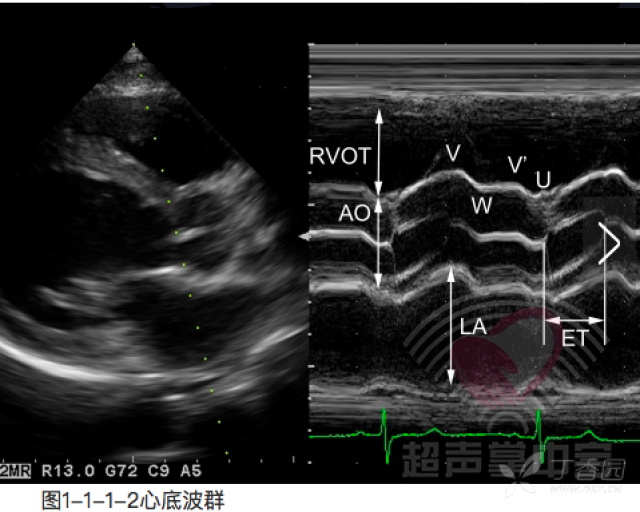

主动脉瓣左冠瓣超声图

主动脉瓣左冠瓣超声图,主动脉三个冠瓣超声图

图1 bav患者主动脉短轴切面:左冠瓣与右冠瓣融合钙化(箭头)